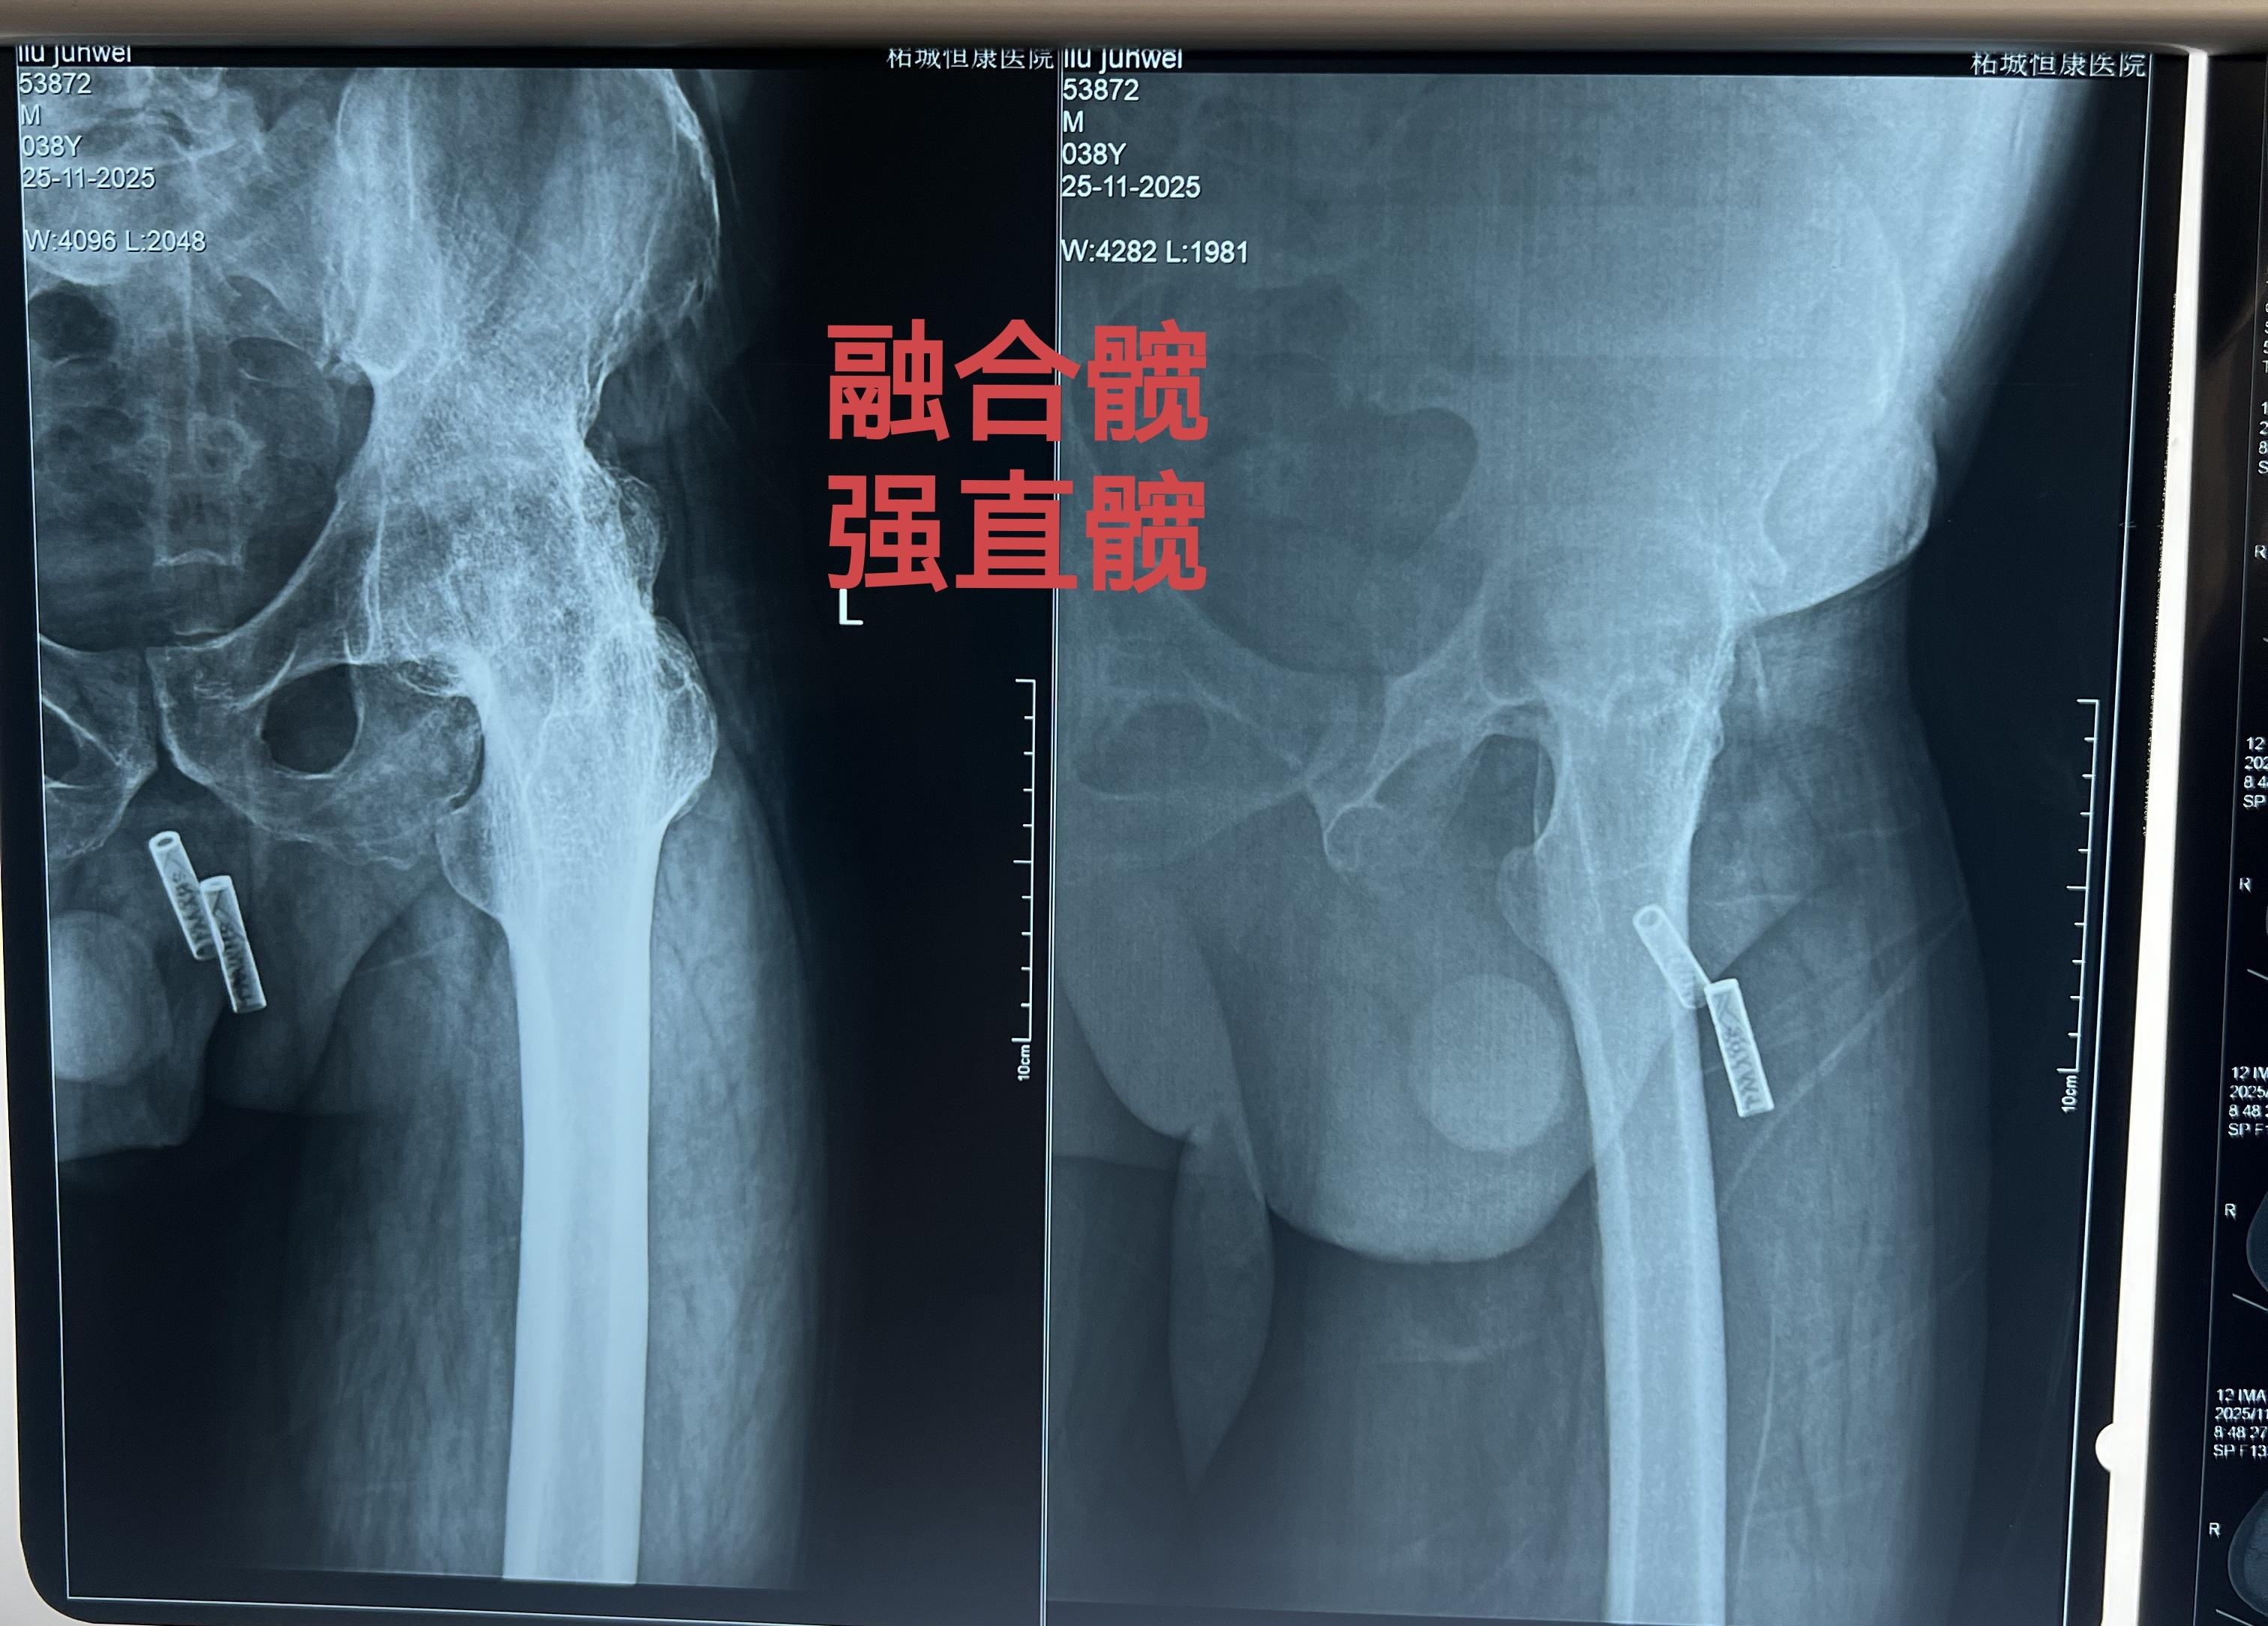

强直髋。强直髋,髋关节无活动度,如有条件,尽早手术,拖得越久,软组织越...